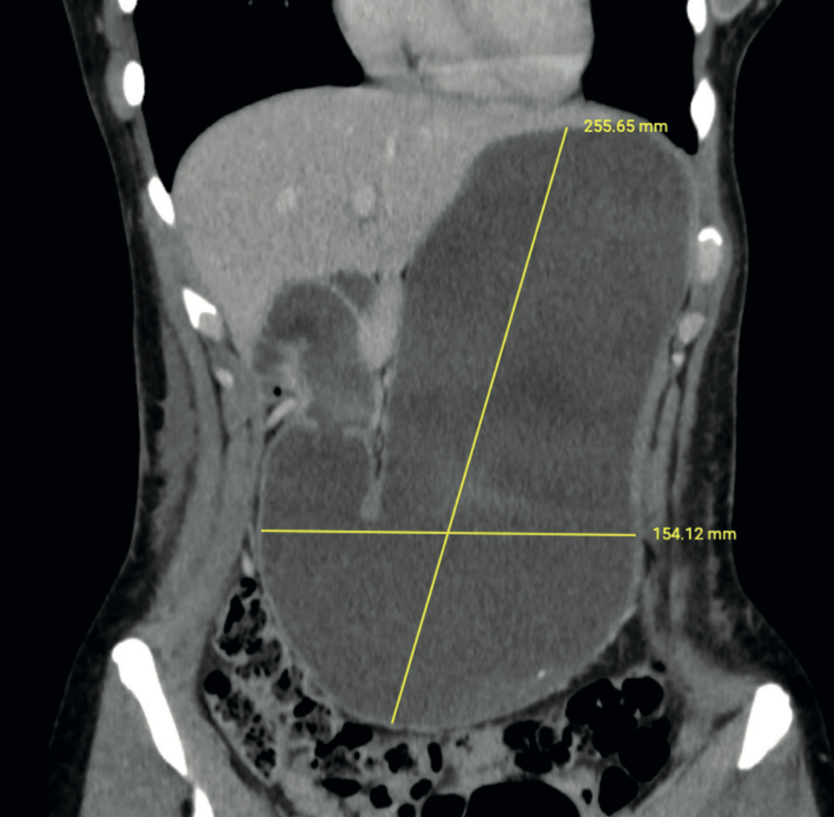

Imágenes y Cirugía

Carolina Andrea Bonomo, Ricardo Felipe Gallardo Ossio, Carlos Luis Torrealba Malpica